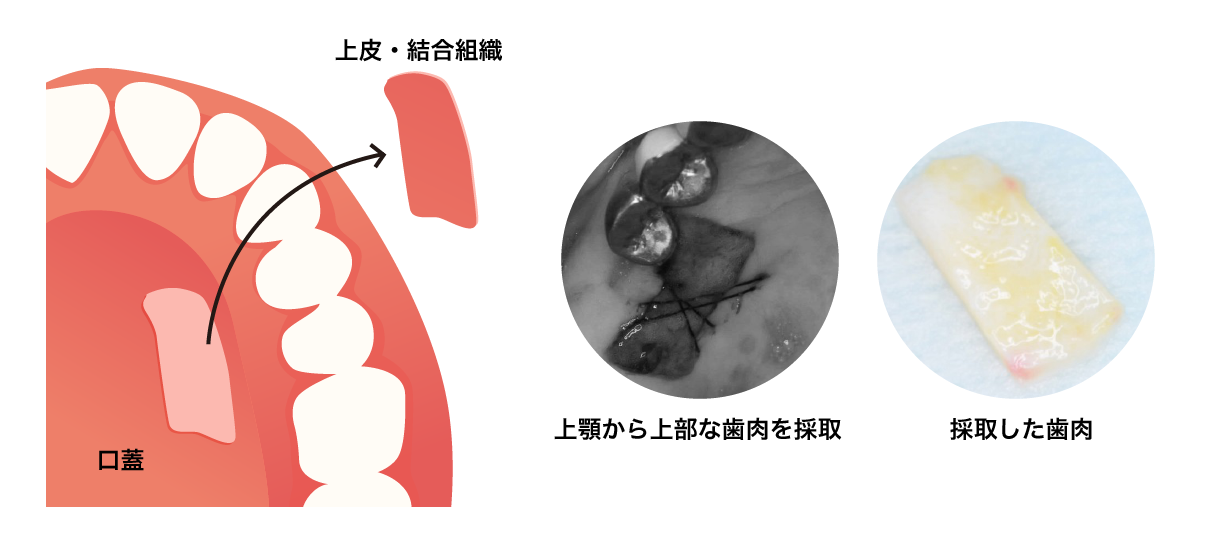

歯肉-歯槽粘膜手術

■弱い歯茎を強くて頑丈な歯茎にする

■歯茎が痩せてしまうのを防ぐ

■根の露出を防ぎ、虫歯を予防する

■歯ブラシのしやすい歯茎にする上顎の裏側の頑丈な歯茎を弱くなってしまった歯茎に移植する